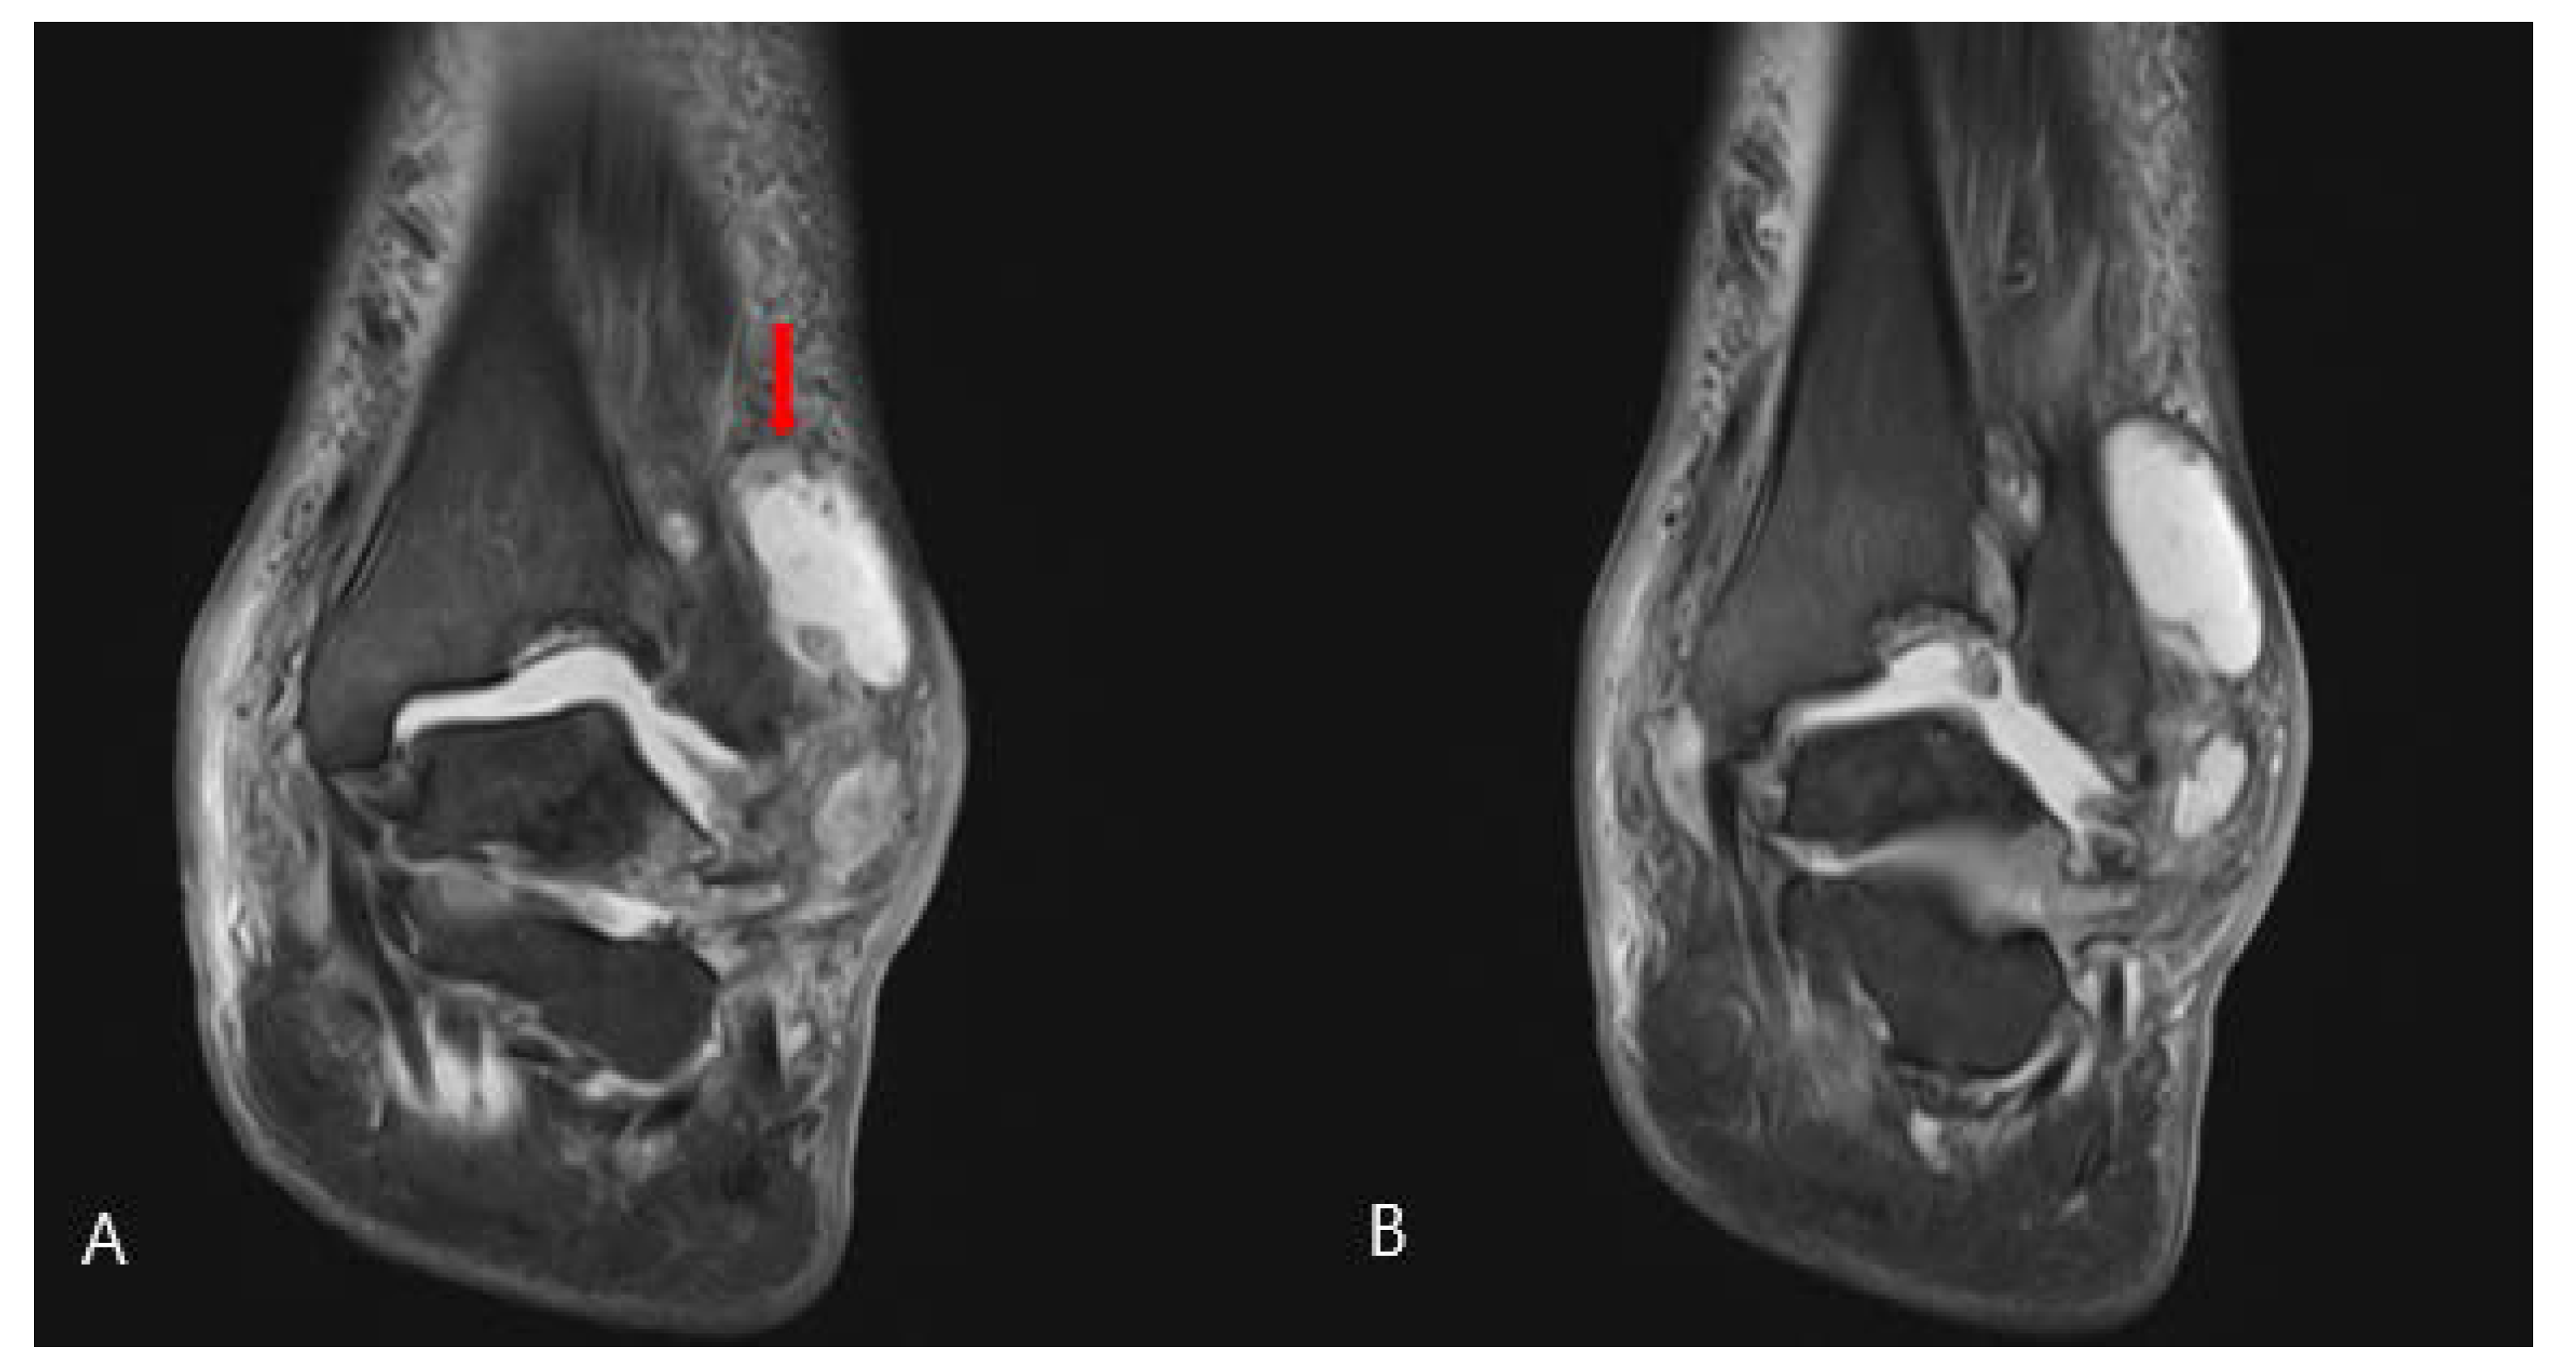

2. Case Presentation

2.1. Preoperative Evaluation